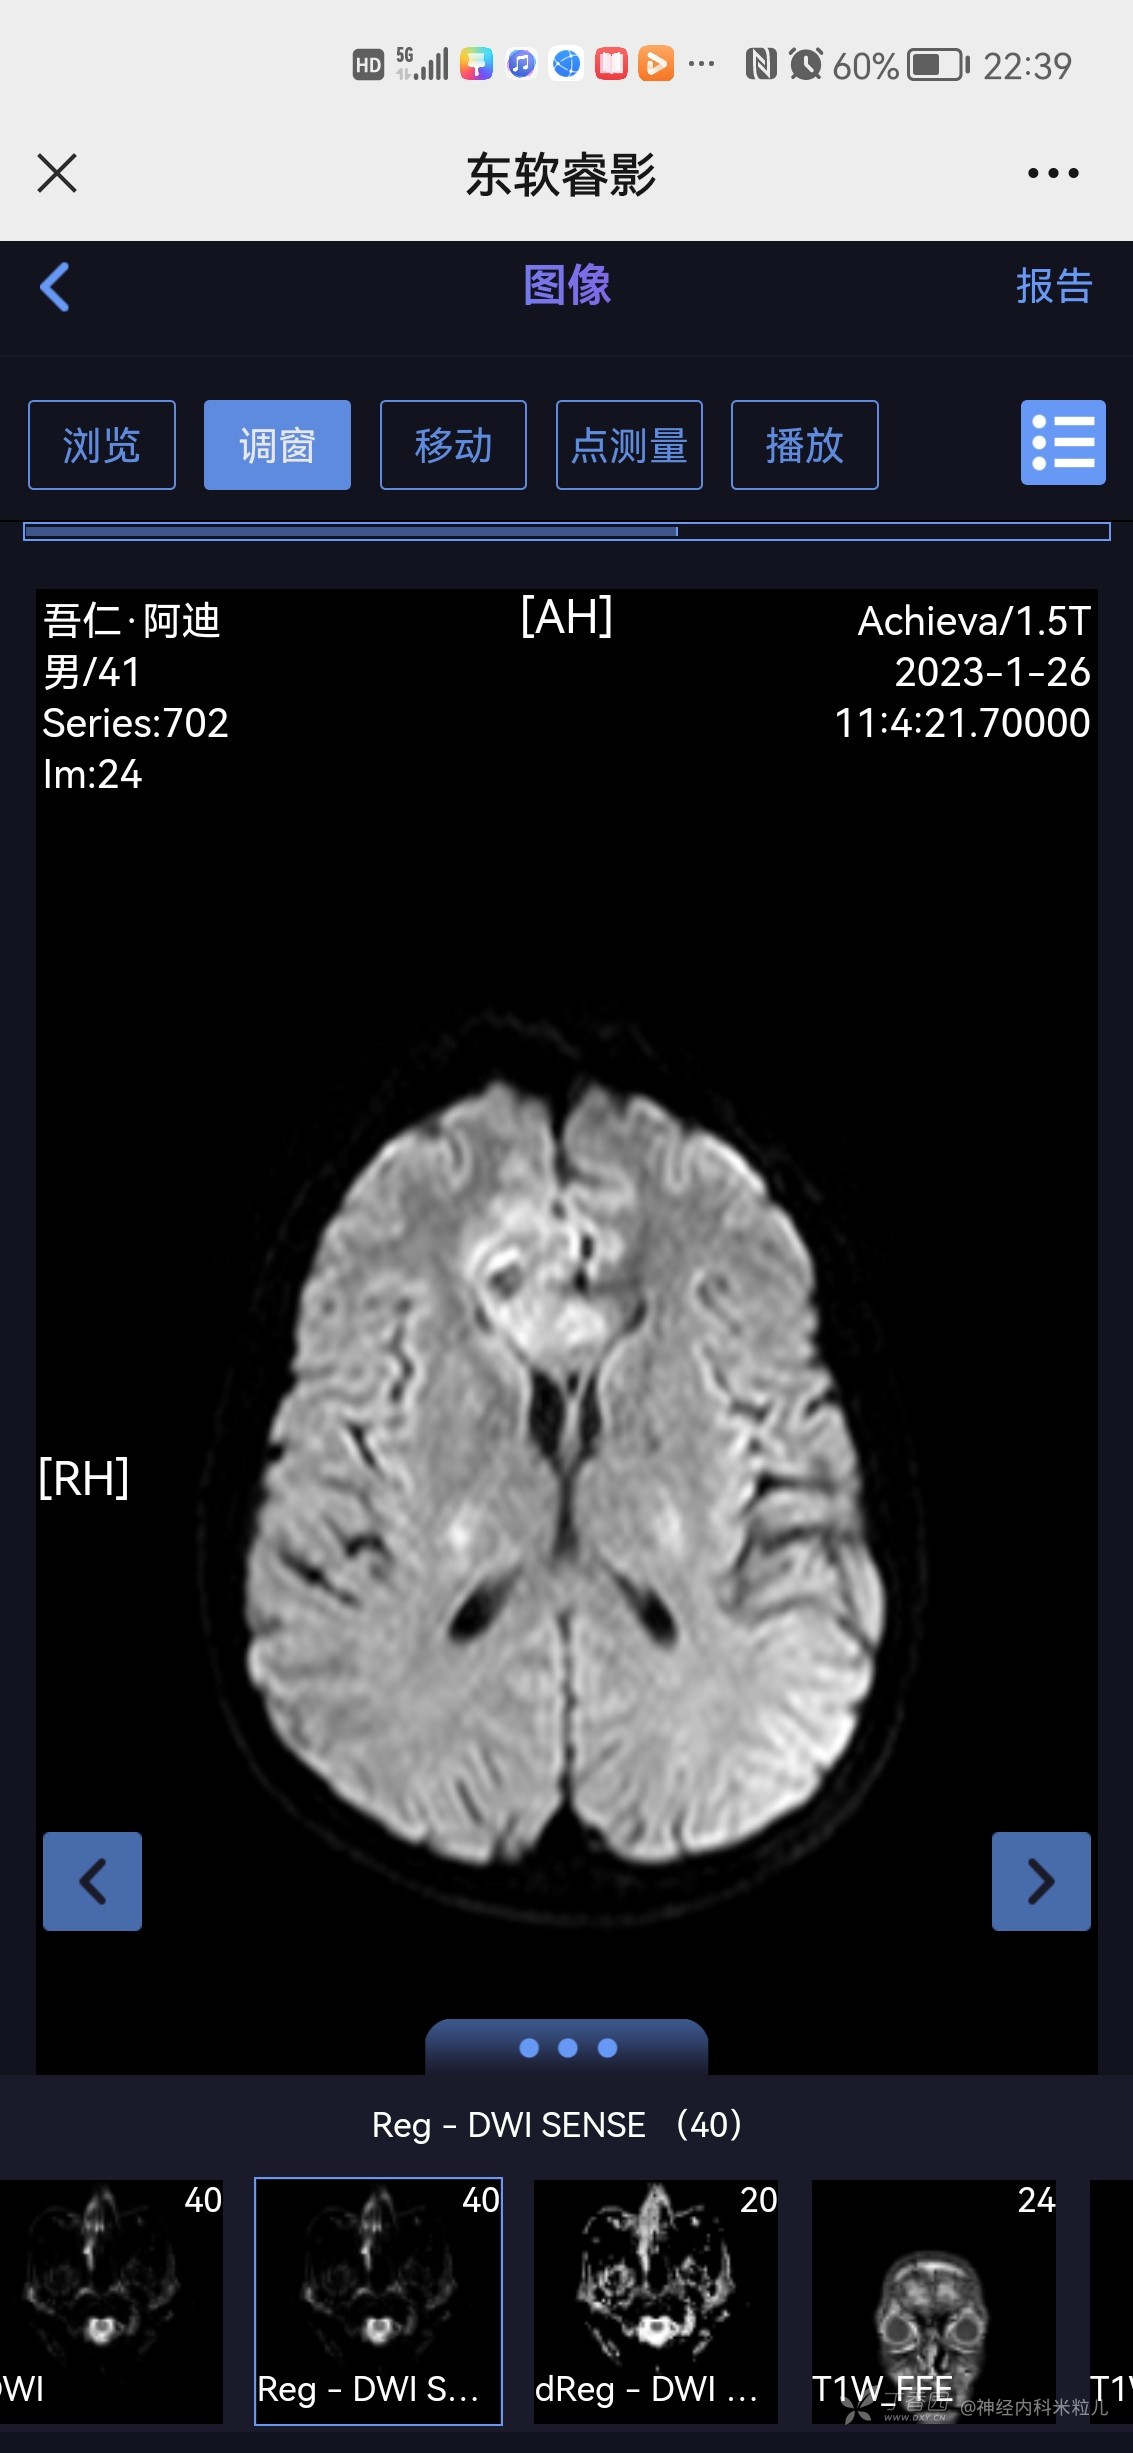

青鹊词等 3人推荐患者家属及本人共诉:于1月6日左右突然出现头痛,呈间断搏动性疼痛,以额部疼痛为主,休息后略好转,白天头痛明显,夜间尚可,并伴有发热,未测体温,发热3天,呈持续发热,并伴有腹泻2天,呈水样便,每日7-8次,无黑便、无血便。就诊当地镇医院,具体诊断及治疗不详,随后症状自行改善,13日患者因手抖,心悸不适来我院内分泌住院治疗诊断甲亢,并给于相应治疗:甲巰咪唑30mg一日次口服,利法沙班15mg一日一次口服,普萘洛尔10mg一日三次口服,查2023年1月18日我院头颅核磁提示:颅内多发异常信号,考虑:感染性病变,建议增强检查。随后患者出院,头痛未再次发作,故今日为进一步查明病因来我院,门诊以“颅内感染、甲亢”收住我科,病程中患者有发热,有头痛、无头晕、无恶心、呕吐、无乏力、有多汗、有心悸、无心前区疼痛、无腹泻,无黑便、无脓血便、饮食睡眠可,近期有体重下降,具体不详。

2023年1月18日我院头颅核磁提示:颅内多发异常信号,考虑:感染性病变,建议增强检查。}